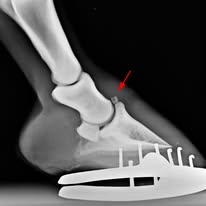

En EQ Plus Veterinaria, nos dedicados al bienestar y la salud integral del caballo tratando de mantener en todo momento su mejor estado físico para la competición con planes integrales de entrenamiento, terapia preventiva de enfermedades y lesiones y programas de rehabilitación y recuperación para la vuelta a los entrenamientos según las distintas disciplinas.

Para todo ello contamos con la experiencia y los medios para que su caballo reciba la mejor atención médica adaptándonos en cualquier situación a sus necesidades. Si desea contratar alguno de los planes de salud que ofrecemos no dude en ponerse en contacto con nosotros.